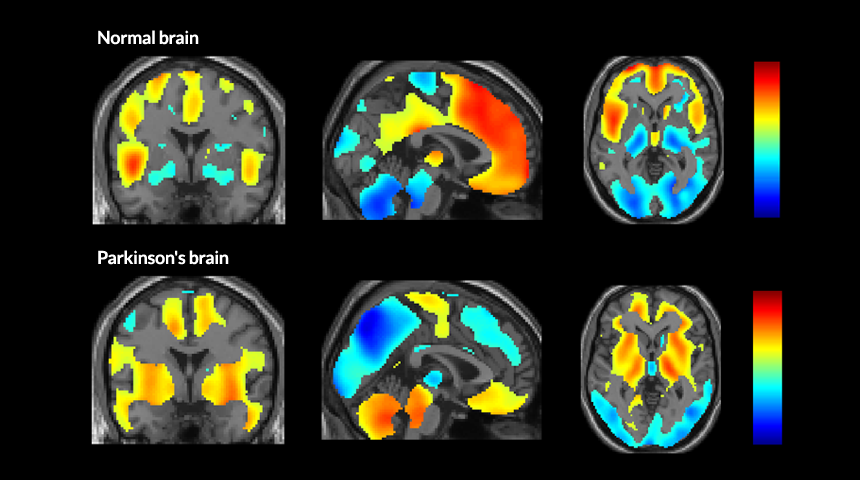

NETWORKING Brain scans reveal the part of the brain that’s active (red shows most activity; blue shows least) when people are not thinking about anything in particular. In healthy people (top row), these coordinated areas of the brain are called the default mode network. But in people with mild to moderate Parkinson’s disease (bottom row), a new, abnormal network takes over.

P. Spetsieris et al/ PNAS 2015, adapted by S. Egts